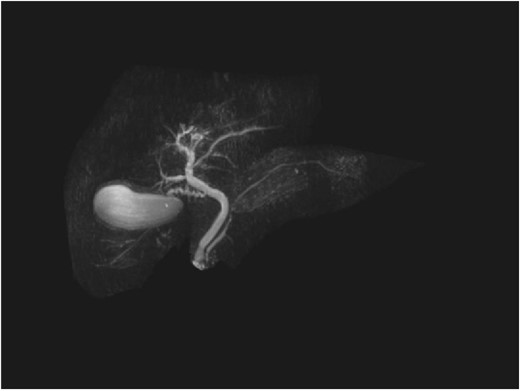

A man in his 70s presented to the emergency department with painless obstructive jaundice with dark urine and pale stools. The patient denied having any fever, nausea, vomiting, or weight loss. Liver function test progressively worsened during the admission peaking at a bilirubin of 287 umol/L (normal 2–20), alkaline phosphatase 694 U/L (normal 30–110), and alanine aminotransferase 160 U/L (normal < 40). Initial assessment on computed tomography and ultrasound raised concerns for primary pancreatic head neoplasm or cholangiocarcinoma (Fig. 1). He subsequently underwent magnetic resonance cholangiopancreatography (MRCP), which showed involvement of the entire common bile duct with no definite stricture or dilatation and no discrete pancreatic head mass (Fig. 2). Positron emission tomography showed abnormal uptake in the intrahepatic and extrahepatic bile ducts, focal uptake in the tail of the pancreas, and lymph nodes in the porta hepatis, retroperitoneum, and right iliac fossa (Fig. 3). Tumour markers revealed a carbohydrate antigen 19-9 (CA19-9) of 3286 kU/L (normal < 34).

Repeat liver function test 1 month later showed dramatic improvement, with bilirubin level at 25 umol/L (normal 2–20), total IgG 13.23 g/L (normal 6.5–15.2), IgG4 1.45 g/L (normal 0.04–0.86), and CA19-9 44 (normal < 34). The steroids were gradually tapered and ceased. Repeat MRI 4 months later showed a normal biliary system with complete resolution of the common bile duct pathology (Fig. 4).